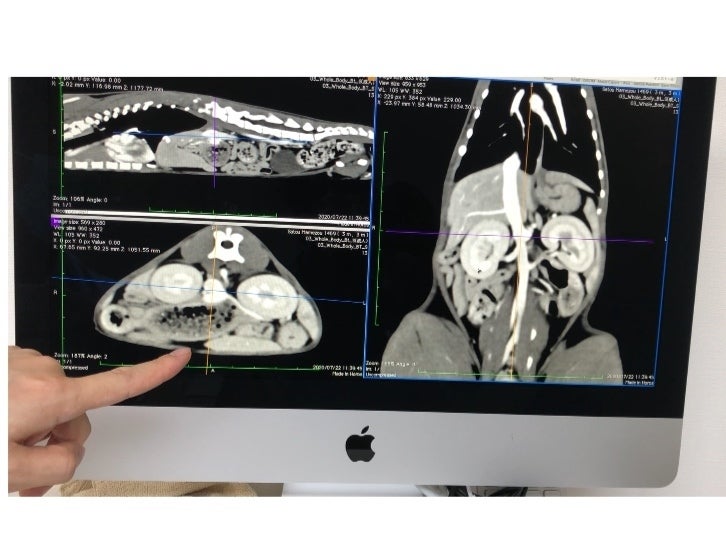

それでも食欲は旺盛で、毎日短時間ですがはしゃいでいる姿はとても可愛くて、手術をできる状態にもっていけるように預かりBABAさんが毎日の投薬に励み、ようやく先日CTスキャンによる検査を受けてきました。

画像診断の結果は、門脈シャントと確定したものの、門脈が異様に細い為かなり難易度が高い手術だということで、1度の手術では対応出来ず、最低でも2回、もしくは3回に分けて手術をしなければならず、1回目の手術代の目安は約20万円、2回目の手術と術前のCT検査で20万円、3回目は15万円ととても高額な目安になると言われました。

プチちゃんのCT検査のご報告です

2020/09/04 00:54こんばんは。今日は預かりBABAから、プチちゃんのCT検査のご報告をさせていただきます。本当は来週検査を予定していたのですが、プチちゃんが一昨日から突然何も口にしなくなってしまい、不安に駆られ病院の先生にご相談をさせて頂き、急遽プチちゃんだけCT検査の日にちを変更して頂けたので、昨日検査に行ってきました。専門の先生と問診をして、CT検査だけではなく内視鏡検査もやった方が良いとのご指示があったので、両方お願いをして夕方検査が無事に終わり、プチちゃんをお迎えに行きました。最初は【動脈管開存症】、次は【右大動脈弓遺残】という仮診断がついていたプチちゃんですが、検査の結果はどちらの病気でもなくて、幼児期に気管に炎症が起きたことから発生したであろう気管支狭窄であることが分かりました。本来プチちゃん位の身体ならば1〜1.2㎝程の太さがある筈の気管支が、プチちゃんは狭いところで4㎜程しかないそうです。6㎜のサイズの内視鏡すら挿入するのがかなり困難を極めたと言われ、この先をどうして行くかをたくさんご相談させて頂きました。有力な可能性はバルーン手術という気管支に管を入れて膨らませる手術だそうなのですが、費用面その他プチちゃんの体力などもまだ不安定なことから、今も炎症を起こしている気管支の炎症をまずは鎮めることが最優先とのことなので、4種類のお薬を2週間投与して、次の検査で方針を決めることになりました。プチちゃんよりも症状的には軽度なリルちゃんも恐らく似たような状況なのだろうと推測されるので、リルちゃんの検査はプチちゃんの次の検査時まで延期することになりました。リルちゃんにも同じお薬を飲ませつつ、少しだけ固形混じりのフードなどをあげで経過を見るように指示があったので、たくさんの不安もありますが、しっかりと様子を確認しながら先生の指示に従いお世話をしていきたいと思います。たくさん頑張ったプチちゃんは、帰りの車の中でキャリーに敷いた毛布をずっとフミフミしていました(;_;)頑張るプチちゃんを引き続き応援してくださいね。コロ助ちゃんマメ蔵ちゃんリルちゃんはとても元気に過ごしていますので、皆の近況報告も頑張ってお届けしたいと思います^_^ もっと見る